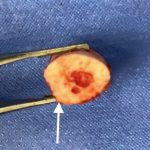

Background: The success of shoulder width narrowing by clavicle reduction osteotomies depends on stable plate and screw fixation. Holding the bones in place until the body starts to knit the two cut ends together requires them to be held in stable proximity for the first month after surgery. Such fixation success depends on having a Read More…